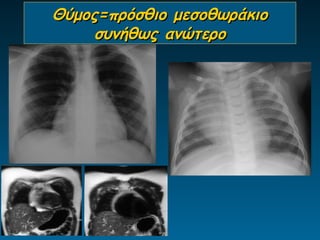

Θύμος=πρόσθιο μεσοθωράκιο

συνήθως ανώτερο

Θύμος στον παιδιατρικό θώρακα

Λέξεις κλειδιά: μαλακός ιστός (wavy), πρόσθιο μεσοθωράκιο

Θεωρείται πρόβλημα: σε ηλικία πάνω από 6 ετών

Θύμος

•     Διεύρυνση ανώτερου πρόσθιου

μεσοθωρακίου

•     Ευγενική τριγωνική δομή

•     Ακεραιότητα πνευμονικών δομών

•     Παιδιά έως 6 ετών

• Εναλλακτικά της α/ας ΥΧ       -ΥΤ-ΜΤ